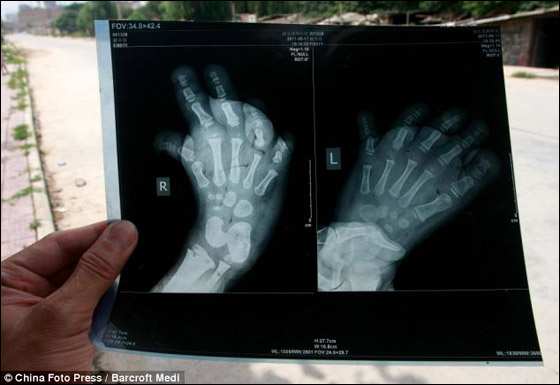

لم تتمكن طفلة صينية من التباهي وسط أقرانها بشراء الأحذية الجديدة كما هي عادة الصغار وذلك بسبب مرض أصابها جعل قدميها كبيرتين بشكل لا يمكنها من ارتداء اي نوع من الأحذية. وتعاني الصغيرة "يويو" من مدينة شيان، بمقاطعة شنشي الصينية والتي تبلغ من العمرة 3 سنوات من مرض لم يوجد له تشخيص يجعلها تمشي بصعوبة حيث تتحرك ببطء وتعاونها جدتها على ذلك. وقد كشفت الأشعة التي أجرتها الجدة لـ "يويو" وجود تشوه وتقوس في القدم، مما جعلها تفقد الأمل في وجود حذاء مناسب لحجم قدميها.